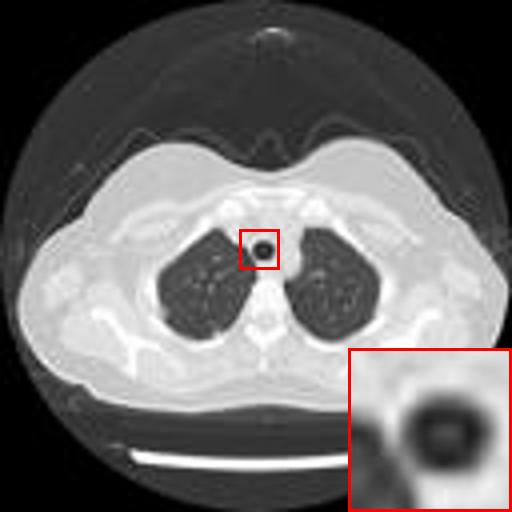

Refer to caption

(a) Original HD image

(b) Bicubic

(c) EDSR

(d) WDSR

(e) T-GAN

Figure 3: Reconstruction results of each algorithm for MRI images of the knee.

The PNSR/SSIM test results for the knee MRI test images for all contrast methods are shown in Table 1. The PNSR/SSIM test results for the abdominal MRI images are shown in Table 2. It’s worth noting that all metrics were calculated on cropped photos in order to eliminate the impact of non-subject areas. The quantitative results show that for knee MRI images, our proposed TT\mathrm{T}-GAN model achieves the best performance on the PSNR/SSIM metrics. For abdominal MRI images, our model essentially achieves optimal performance, with individual image WDSR slightly outperforming our model. The experimental results cousin that our model is more suitable for medical image super-resolution reconstruction than the existing deep learning-based image super-segmentation models.

We likewise give the visualization comparison results for each comparison algorithm, as shown in Fig. 3 and Fig. 4. It can be seen that the reconstructed images based on bicubic interpolation and deep learning based EDSR and WDSR both show oversmoothing phenomenon and some loss of detail information of the images. In contrast, our T-GAN performs better for the reconstruction of detail information due to the texture Transformer structure.